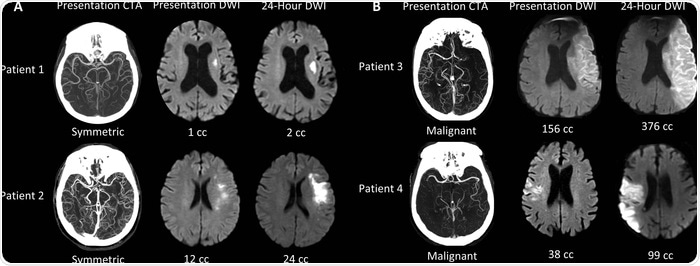

It turns out that the growth of the ischemic core varies widely amongst patients. Our research, confirmed by work at other centers, shows that nearly half of all patients have a slow growth pattern and may be treated 24 hours after stroke onset, and perhaps even later.

We are creating a machine learning algorithm that can identify LVO patients with symmetric collateral circulation that is a marker of small cores that are growing slowly. This is one of several algorithms that we are combining into a suite of algorithms that are capable of capturing all of the key information for the evaluation of the acute stroke patient.